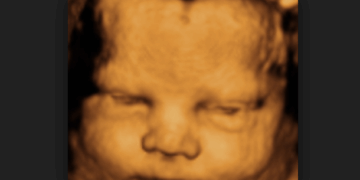

A Natrona County judge has temporarily blocked Wyoming’s Human Heartbeat Act, a law aimed at protecting unborn babies from abortion once the baby’s heartbeat is detectable. Natrona County District Judge Dan Forgey issued the temporary…